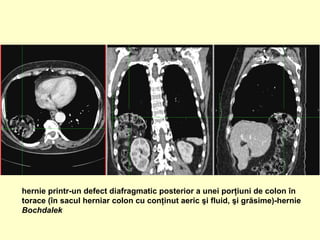

hernie printr-un defect diafragmatic posterior a unei porţiuni de colon în

torace (în sacul herniar colon cu conţinut aeric şi fluid, şi grăsime)-hernie

Bochdalek